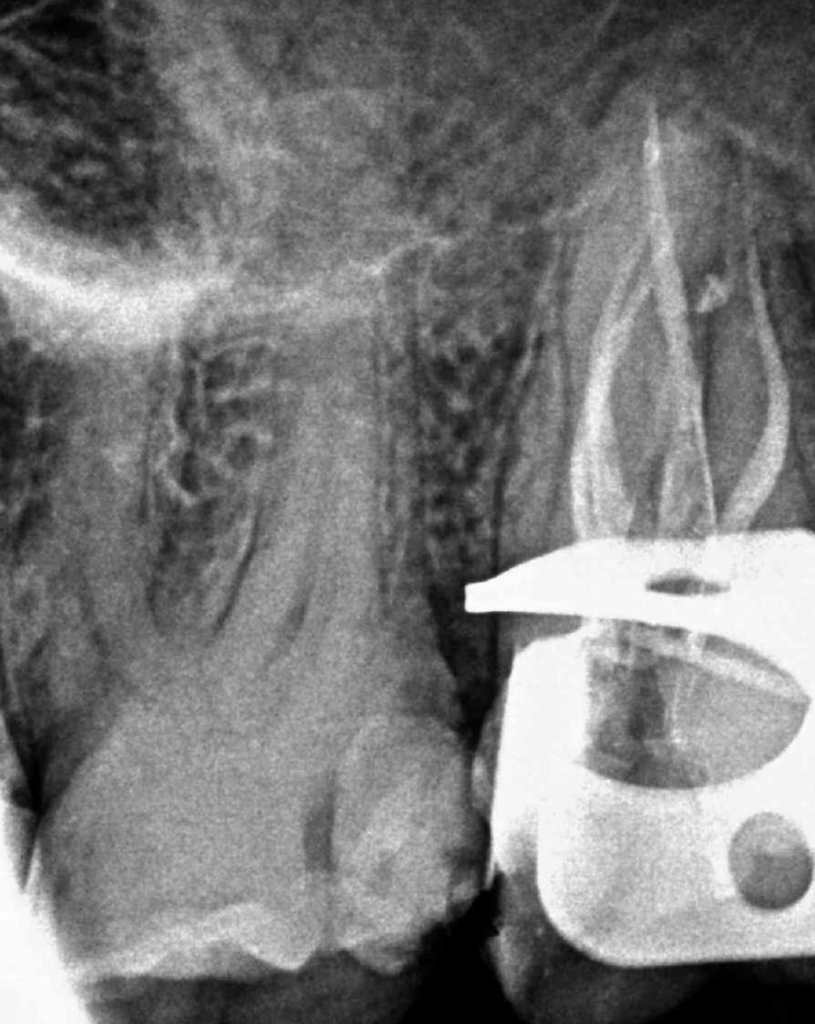

Reco preendo + 4 conductos molar superior